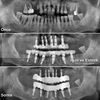

Implant tedavisi